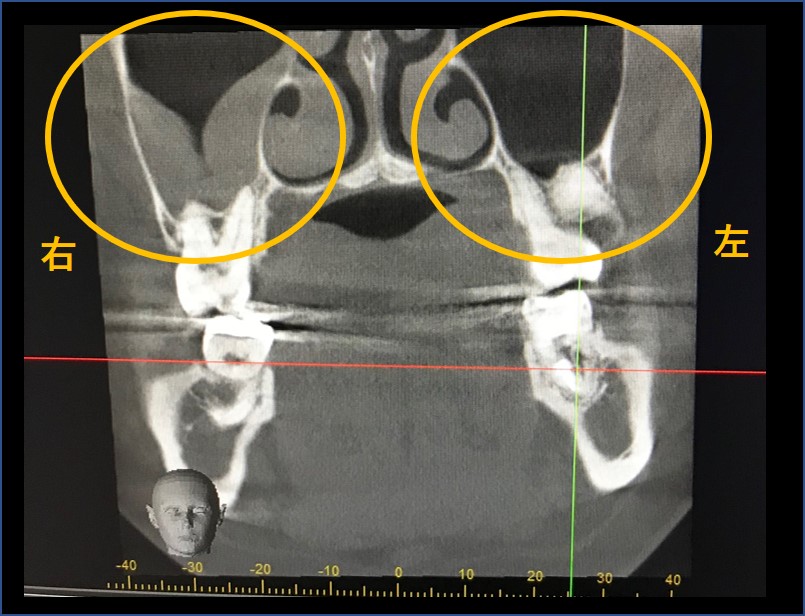

パノラマエックス線写真で矢印部分の歯が欠損しています。ここに2本のインプラントを埋入する予定で治療を行いました。オレンジ線の部分が下顎管と呼ばれます。この中に太い神経線維や血管が走行しており、この位置までインプラントを入れてしまうと唇や歯の感覚麻痺がおこるため慎重に処置を行う必要があります。

パノラマエックス線写真では、この下顎管や骨の高さのおおよその位置は把握できますが、骨の中でどのように下顎管が走行しているのか詳細はわかりません。

そのため、術前にCT撮影が必要になります。CT撮影を行わなくてもインプラント治療は可能ですが、より安全に行うために必要であるといえます。

左写真が前からの断層写真です。インプラント(真っ白に写っている部分)と下顎管(オレンジ矢印)には安全な距離が保たれています。右写真は横からの断層写真です。オレンジ線が下顎管です。インプラントと下顎管には距離があるため、問題なく2本のインプラントが埋入できました。